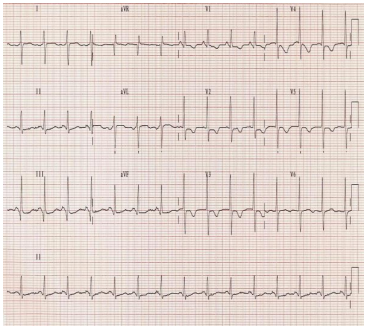

Homem de 28 anos, sem comorbidades e com uma dose prévia da vacina para Covid-19 teve episódio gripal moderado e com RT-PCR positivo para Covid. Após o isolamento adequado e boa evolução, teve quadro súbito de dor no peito em pontada, localizada e com dispnéia. Ao exame, apresentava-se com FR = 32irm, FC 100bpm, PA 140x90mmHg, Sat 90%. O ECG realizado foi o seguinte:

Leia o caso a descrito a seguir para responder às questões 37 e 38.

Homem de 28 anos, sem comorbidades e com uma dose prévia da vacina para Covid-19 teve episódio gripal moderado e com RT-PCR positivo para Covid. Após o isolamento adequado e boa evolução, teve quadro súbito de dor no peito em pontada, localizada e com dispnéia. Ao exame, apresentava-se com FR = 32irm, FC 100bpm, PA 140x90mmHg, Sat 90%. O ECG realizado foi o seguinte:

De acordo com os dados apresentados, a principal hipótese diagnóstica é de